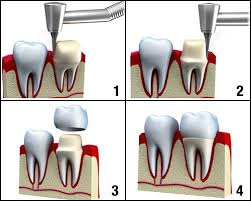

Then we prepare your teeth and take impressions.

Tooth preparation is required.

Veneers or crowns are made and tried in.

Then are cemented on and you go home with your new smile.

Before dental veneers can be placed on the teeth, the surface of the teeth must be prepared for bonding.

After administering a local anesthetic, your dentist will reduce approximately half a millimeter from the surface of the teeth.

You’ll then bite into a mold that will be used to form your Veneers in a dental lab. Ready Veneer is fitted on tooth by bonding and adjusting for shape and color.